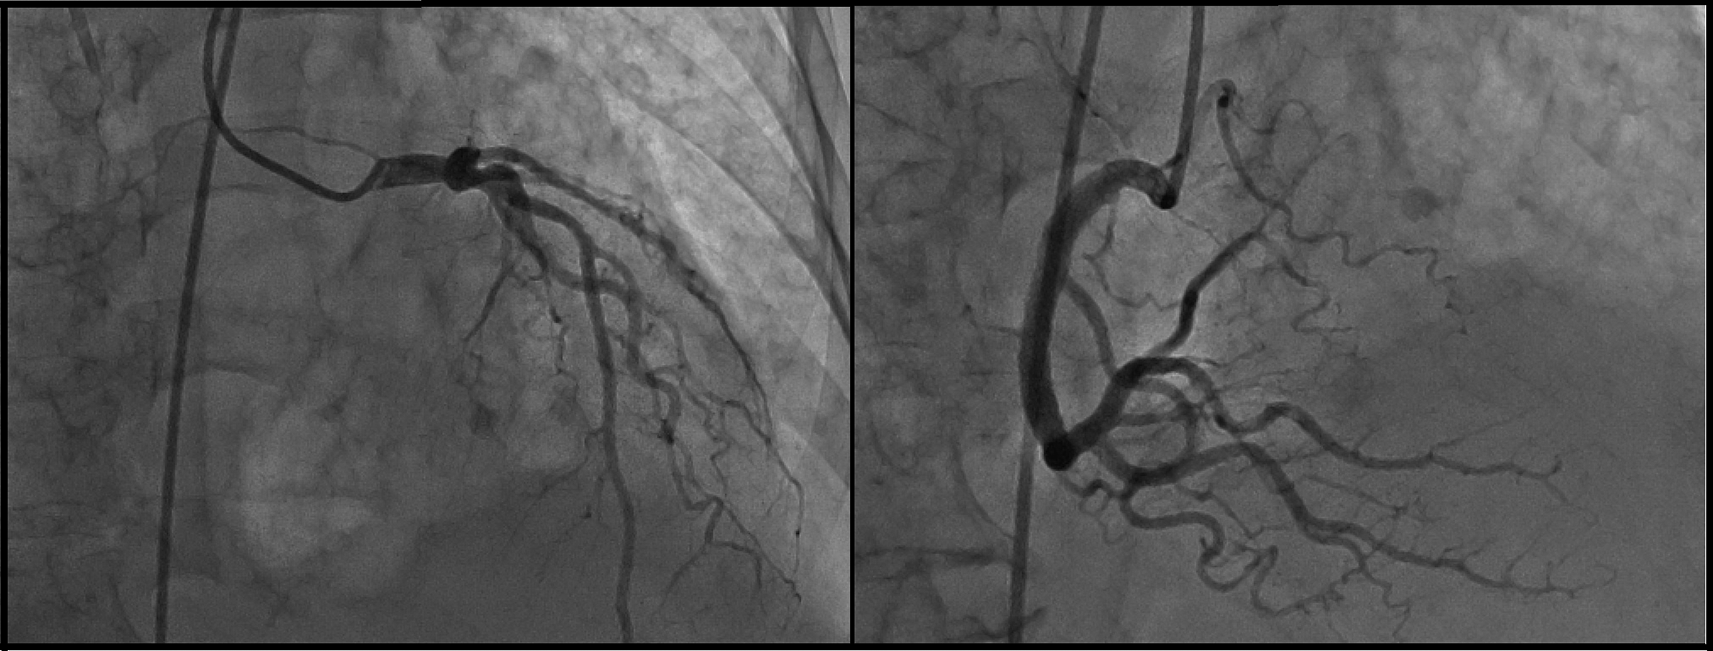

The day after she was admitted to the ICU (post-operative day four), the patient presented with atrial fibrillation with high ventricular response; then, amiodarone infusion was administered reverting the dysrhythmia. At the moment of the dysrhythmia, serial ECG was performed in which marked negative T-waves in II, III, and augmented vector foot (aVF) leads, and all precordial leads were observed (Figure 1). Neither ST-segment disorder nor pathologic Q-waves were present. For this reason, the cardiology department performed echocardiography for the second time (post-operative day eight) where 44% LVEF systolic dysfunction, dilated left ventricle, mild mitral insufficiency, and severe aortic insufficiency with marked apical dyskinesia and contraction of basal segments were evidenced. In the cineangiogram, neither lesions nor occlusion were found in the trunk of the left coronary artery, anterior descending artery, circumflex artery or right coronary artery (Figure 2).

Suspecting of ACS, anti-ischemic therapy was begun with digoxin 0.125 mg per day and cardiac enzymes were required, which resulted in troponin T elevation (0.35 ng/ml) and troponin I (0.55 ng/ml). Considering these results, coronarography was performed where no coronary lesions with natriuretic peptide (pro B-type natriuretic peptide (ProBNP)) 35,000 pg/ml (normal values: 0-222 pg/ml) were evidenced.